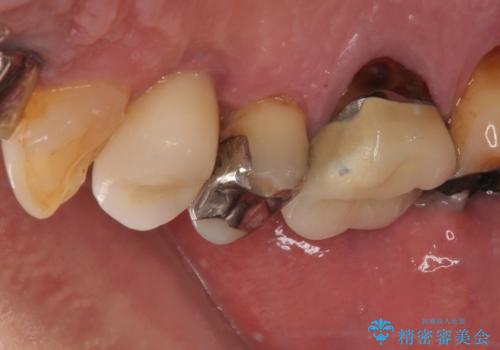

- 抜歯が必要なのでは?と近医で言われ、歯の保存を希望して来院された患者様です。

既に別の部位にインプラント治療を受けており、そのときの治療期間と苦労を鑑みて、何とか歯を残したいとのことで来院されました。

該当歯の状態としては何とか保存可能でしたが、予後不良のため、将来的にインプラント治療が必要となる可能性の高い状態でした。

当院での根管治療および歯周外科治療を併用した保存療法、並びに1DAYインプラントによる短期間インプラント治療の双方をご説明し、即日でインプラント治療を選択されました。

仮歯を用意した上で、抜歯即時埋入・即時荷重インプラントによる補綴治療を行うこととしました。